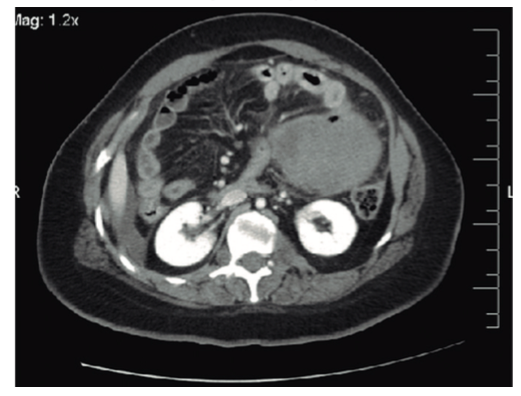

A la palpación abdominal se detecta una masa dolorosa en flanco derecho, y en la ecografía solicitada de urgencia se confirma la presencia de una tumoración de 9 x 9 x 7 cm dependiente del intestino delgado con líquido libre (Figura 1). Se realizó una laparotomía y se constató una peritonitis purulenta generalizada secundaria a tumoración perforada en íleon distal compatible macroscópicamente con tumor estromal gastrointestinal, conocido como GIST (Figura 2), por lo que se realizó resección ileocecal con anastomosis ileocólica.

En cuanto al diagnóstico, las técnicas de imagen aportan datos anatómicos que definen la relación del tumor con las estructuras adyacentes y permiten evaluar la resecabilidad y posibilidades de tratamiento.4-6 El método diagnóstico de elección es la tomografía computada (TC), que nos confirma la heterogeneidad de la masa, la localización mesentérica y la relación con las estructuras vasculares y parenquimatosas adyacentes.1